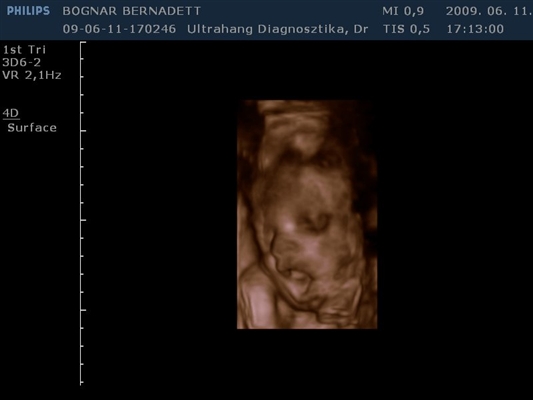

Kb. 3,5 hete én is voltam 4D-n és egy egész jó kis kép kerekedett belőle, majd felteszem.